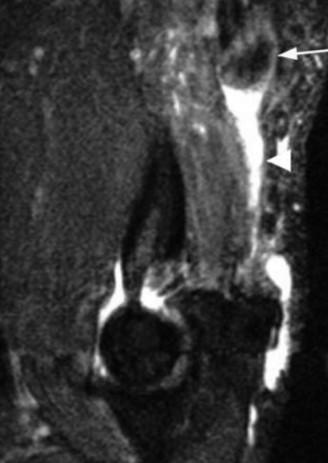

The correct answer is (E). Although the diagnosis is most consistent with a distal triceps tendon rupture, this patient has 3/5 motor strength. An MRI must be obtained in this instance to assess the location and degree of tendon involvement (see Fig. 2–123). Physical examination and strength grading can be difficult and inconsistent in the acute setting, even leading to some missed diagnoses. Partial ruptures may present with profound strength deficits, whereas complete ruptures may exhibit little or no strength deficit due to compensation from an intact lateral triceps expansion or the anconeus. This makes an MRI essential for accurate diagnosis and preoperative planning. In general, tears <50% can be managed conservatively with satisfactory results. Partial tears >50% are managed on an individualized basis. They can be managed nonsurgically in sedentary or medically infirm individuals, with repair indicated for active or younger individuals. Complete tears are usually best treated surgically.

Figure 2–123_MRI depiction of retracted triceps tendon (_white arrow) and fluid filled gap (arrowhead).